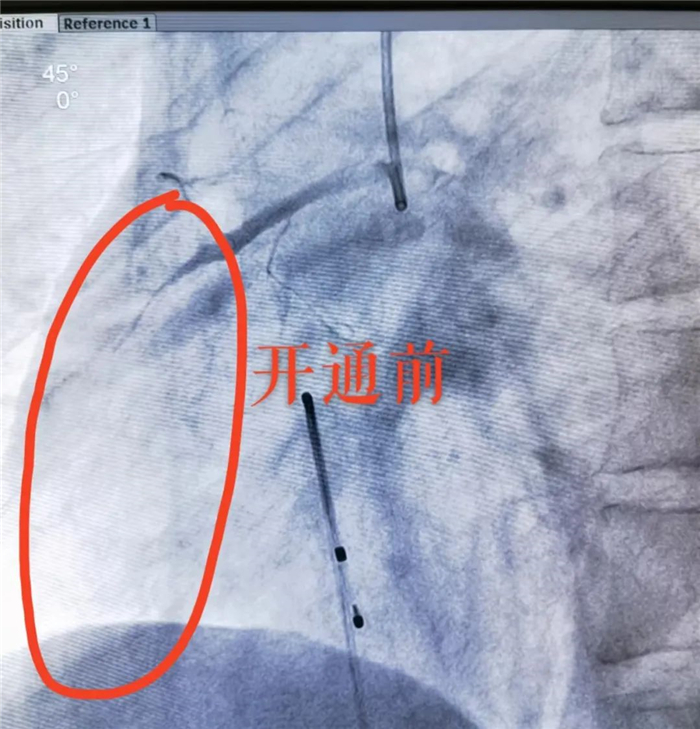

造影顯示,患者右冠狀動(dòng)脈完全閉塞、血供中斷,這也正是導(dǎo)致其心肌梗死的“罪魁禍?zhǔn)住?

分秒必爭(zhēng)!在大家精細(xì)操作、緊密配合下。安裝臨時(shí)起搏器保駕,終于為患者順利打通閉塞血管,使瀕死的心肌恢復(fù)血供!患者轉(zhuǎn)危為安。轉(zhuǎn)ICU繼續(xù)監(jiān)護(hù)治療。該例搶救,從接診入院到完成手術(shù),僅用時(shí)40分鐘!